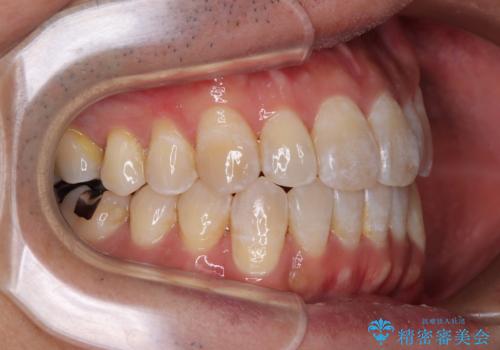

- 前歯のデコボコとクロスバイトを気にして来院された患者様です。

40代半ばであり、あまり周りに気を遣われずに治療を進めたいとのことで、インビザラインにて矯正治療を行うこととしました。

毎日22時間の装着時間をきっちりと守ってくださり、1年半かけずに思い通りの歯列に仕上げることができました。